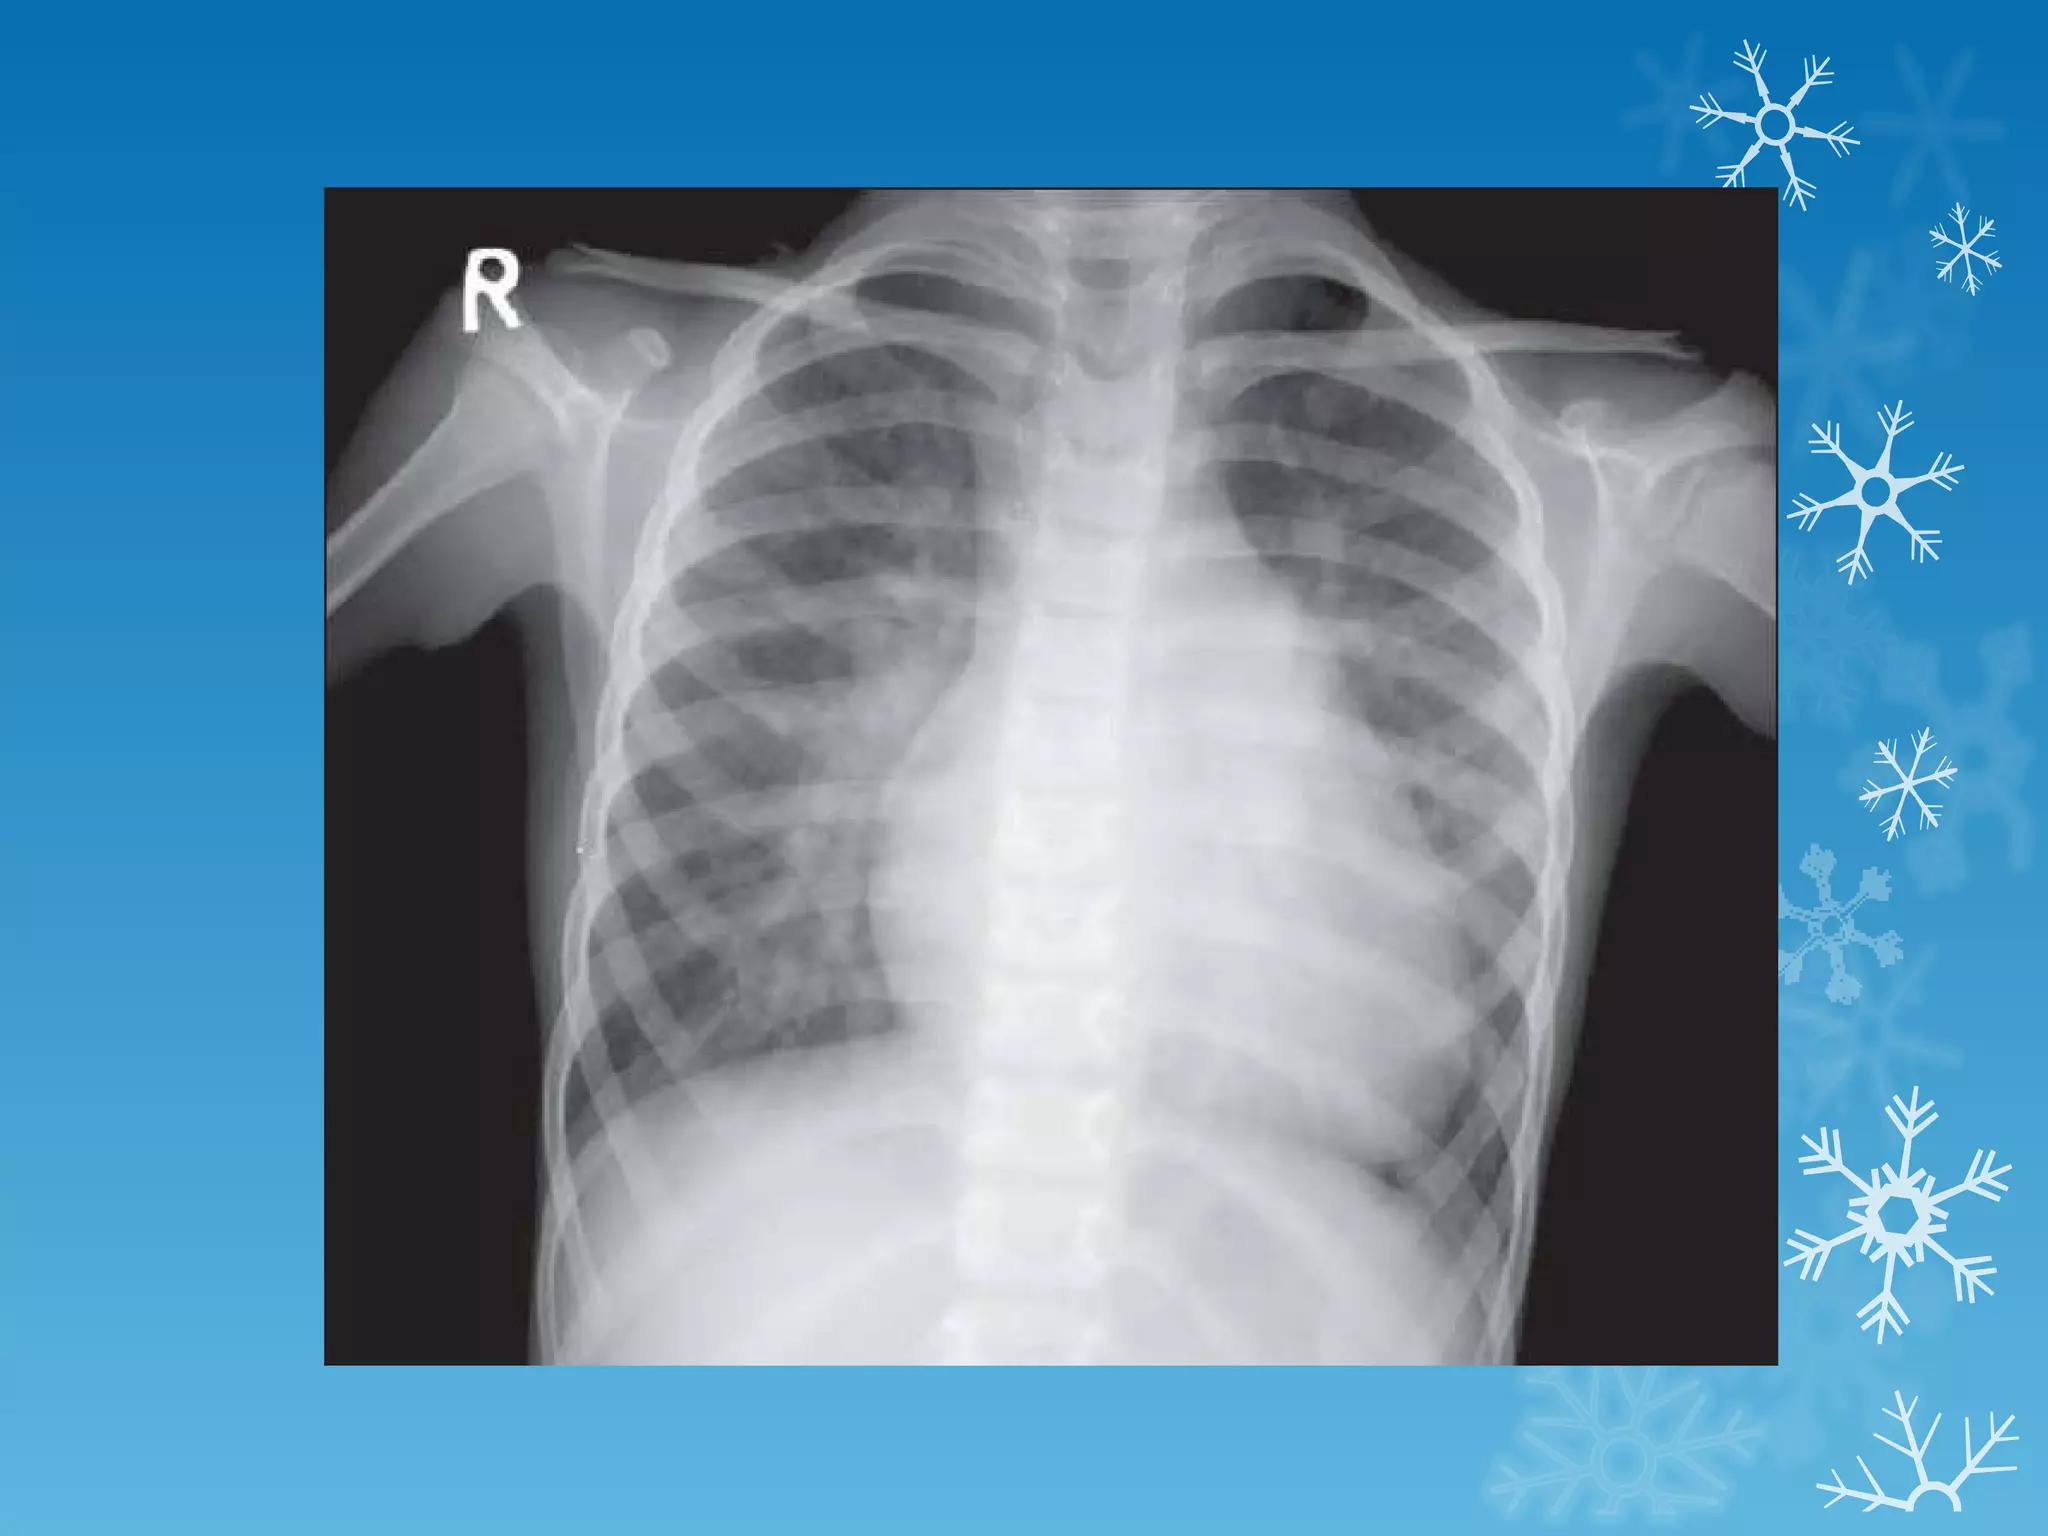

This document discusses chest x-ray interpretation and provides guidance on evaluating x-rays. It explains that tissue density determines how an x-ray beam penetrates, with denser tissues appearing whiter and less dense tissues appearing blacker. It also outlines different chest x-ray views and factors to consider like patient orientation, age, gender, and rotation. Abnormalities are described as appearing too white, too black, too large, or in the wrong place. The document stresses a systematic approach of identifying, localizing, describing lesions, and providing differential diagnoses.